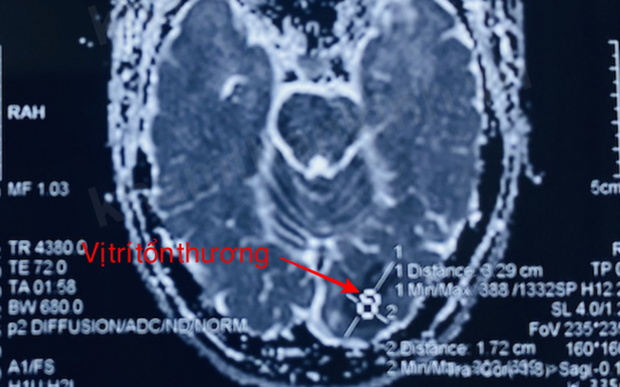

Sau đó, bệnh nhân được chuyển vào Bệnh viện Hữu nghị Việt Tiệp với tình trạng thị lực của mắt phải còn 8/10, đồng thời kết quả kiểm tra đáy mắt và mắt trái đều bình thường. Kết quả cộng hưởng từ sọ não chỉ ra hình ảnh nhồi máu não ở hạch thần kinh bên trái.